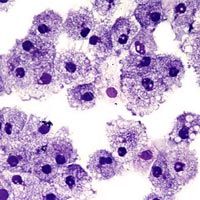

First, the foreskin is delicate and very susceptible to tears during intercourse. This provides an easy entry point for the AIDS virus, which creeps in through the torn blood vessels. But the bigger issue is the high concentration of a type of white blood cell in the foreskin. Langerhans cells are present in the foreskin, and especially in the underside of the foreskin, in very high concentrations. These cells are "sentinel cells" of the immune system. Located in the skin, they are some of the first to detect and pick up an antigen for processing. An antigen is a foreign substance that triggers an immune response when it gets in the body. A virus, such as HIV, contains antigens.

Because there are so many Langerhans cells in the foreskin, and because these particular cells seem to be excellent at binding to HIV antigens, when the foreskin tears during sex with an HIV-infected woman, there is a very good chance that those blood cells are going to contact and bind to the virus. Langerhans cells are supposed to trigger the immune system's antibody response that fights off the virus; but once HIV gets in, the immune system can't seem to fight it effectively. Once the foreskin is removed, the increased risk of blood exposure and the higher concentration of HIV-receptors in that blood disappears.